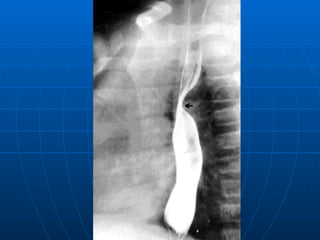

Quiste broncogénico Compresión traqueal

Anillo vascular congénito

Diagnóstico diferencial en SOB ETIOLOGÍA CARACTERÍSTICAS  LABORATORIO  Malformación vascular  Estridor  Hallazgo radiológico Estudio imagenológico (radiología, esofagograma, eco doppler , TAC con contraste, angiografía, RNM).  Endoscopía  Malformaciones pulmonares  Neumopatía recurrente o  prolongada.  Hallazgo radiológico  Ecografía prenatal  Rx. de tórax, TAC de tórax, angiografía  Disquinesia ciliar  Patología sinusal y ótica  Situs inverso, Bronquiectasias Rx. Tórax Rx. senos paranasales  Biopsia epitelio respiratorio.